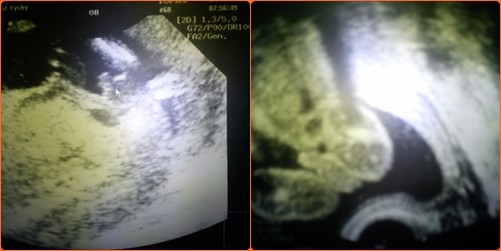

mój bąbelek po prostu pokazał pupę tak jak nie chciał pokazać się prywatnie tak na fundusz wystawił tyłek z dwoma jajeczkami ...nawet się nie spodziewałam ,że mam synka a tam takie wielkie dwa jajeczka

TO POPRZEDNIA CIĄŻA I MOJ MAŁY BEZWSTYDNIK.. I ZERO WĄTPLIWOŚCI ŻE MOŻE SIĘ ZDARZYĆ DZIEWCZYNKA.. oj oby teraz było na odwrót